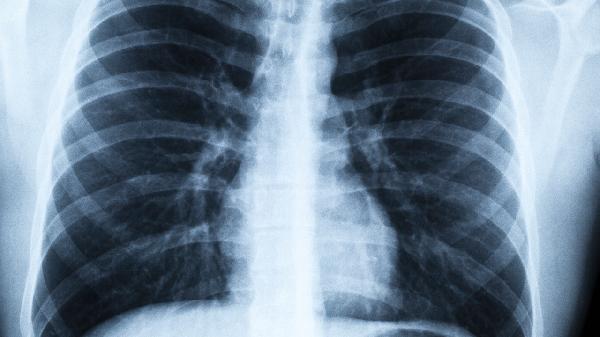

除药物预防外,日常需保持室内通风,勤洗手并规范佩戴口罩。饮食注意补充优质蛋白和维生素C,适量运动维持免疫功能。出现持续发热、咳嗽加重等症状应及时就医,避免自行用药延误治疗。高危人群可定期进行肺功能检查和胸部影像学评估。